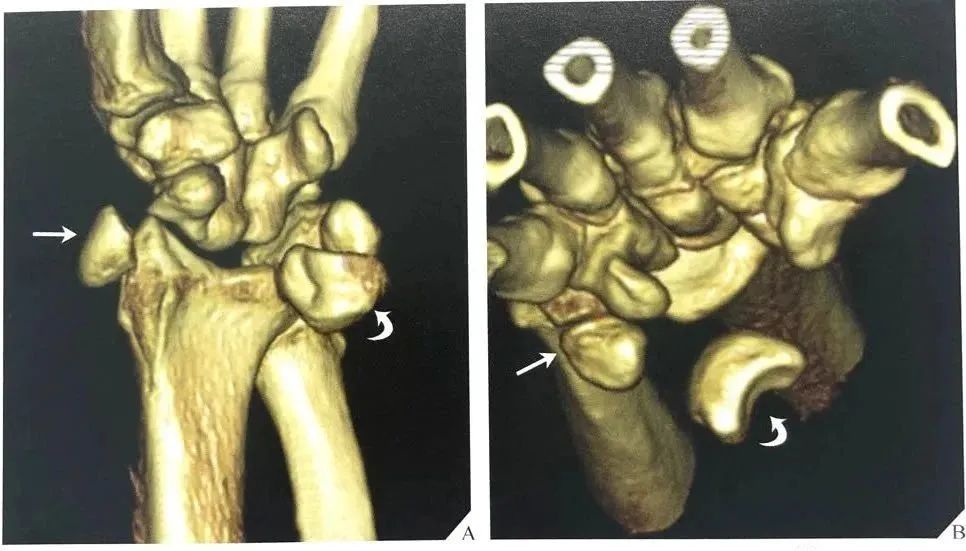

同样的,在背掌位投照时,由舟骨远端凹面、月骨、三角骨所构成的弧线 II 的中断和相伴随的月骨三角形外观也可以诊断月骨脱位(图22B), 月骨脱位也能有效地从CT上显示,尤其是3D CT的重建图像(图23)。

图22 月骨脱位。(A)在腕关节侧位像上,月骨脱位时脱离由第三掌骨、头状骨和桡骨远端的长轴排列,月骨向掌侧旋转和移位。(B)背掌位投照显示弧线 II 在月骨位置中断。注意月骨的三角形外观及月骨脱位的征象。

图23 骨脱位伴舟骨骨折的3D CT表现。腕关节前位(A)及轴位(B)重建图像示舟骨骨折(箭头)和月骨掌侧移位(弯箭头)